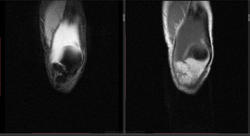

Мужчина 1963 г.р. Жалуется на боль в левом коленном суставе около 6 мес, в последний месяц стало совсем тяжко. Со слов заболел зимой, когда во время прогулки коленки сильно замерзли. Сам думаю на асептический некроз, но смущает множественность поражения.

Дмитрий, я в заболеваниях суставов не дока, но трабекулярный отек вкупе с выпотом может быть обусловлен воспалительными изменениями , но полностью начальные проявления аваскулярного некроза не могу отрицать.

я бы не поставил аваскулярный некроз. если исключена травма, дифференцировать с артритом.

Хрящ не поврежден, для артрита...